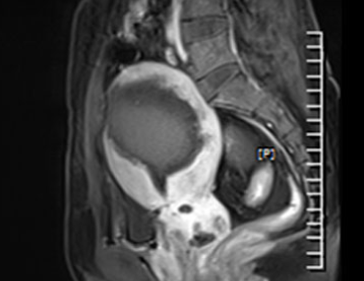

시술 후